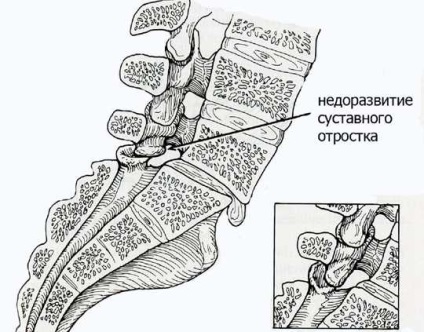

Aspectul displazic se datorează malformații fetale înnăscute și intrauterine sau ereditatea rău.

Fanta în funcție de locația patologiei sunt următoarele tipuri:

Într-o formă tipică de arc cleft interarticular localizate în decalajul. Când retrosomaticheskoy - în zona rădăcinii arcului. localizare atipică - diferența dintre comun și baza arcului vertebrale.